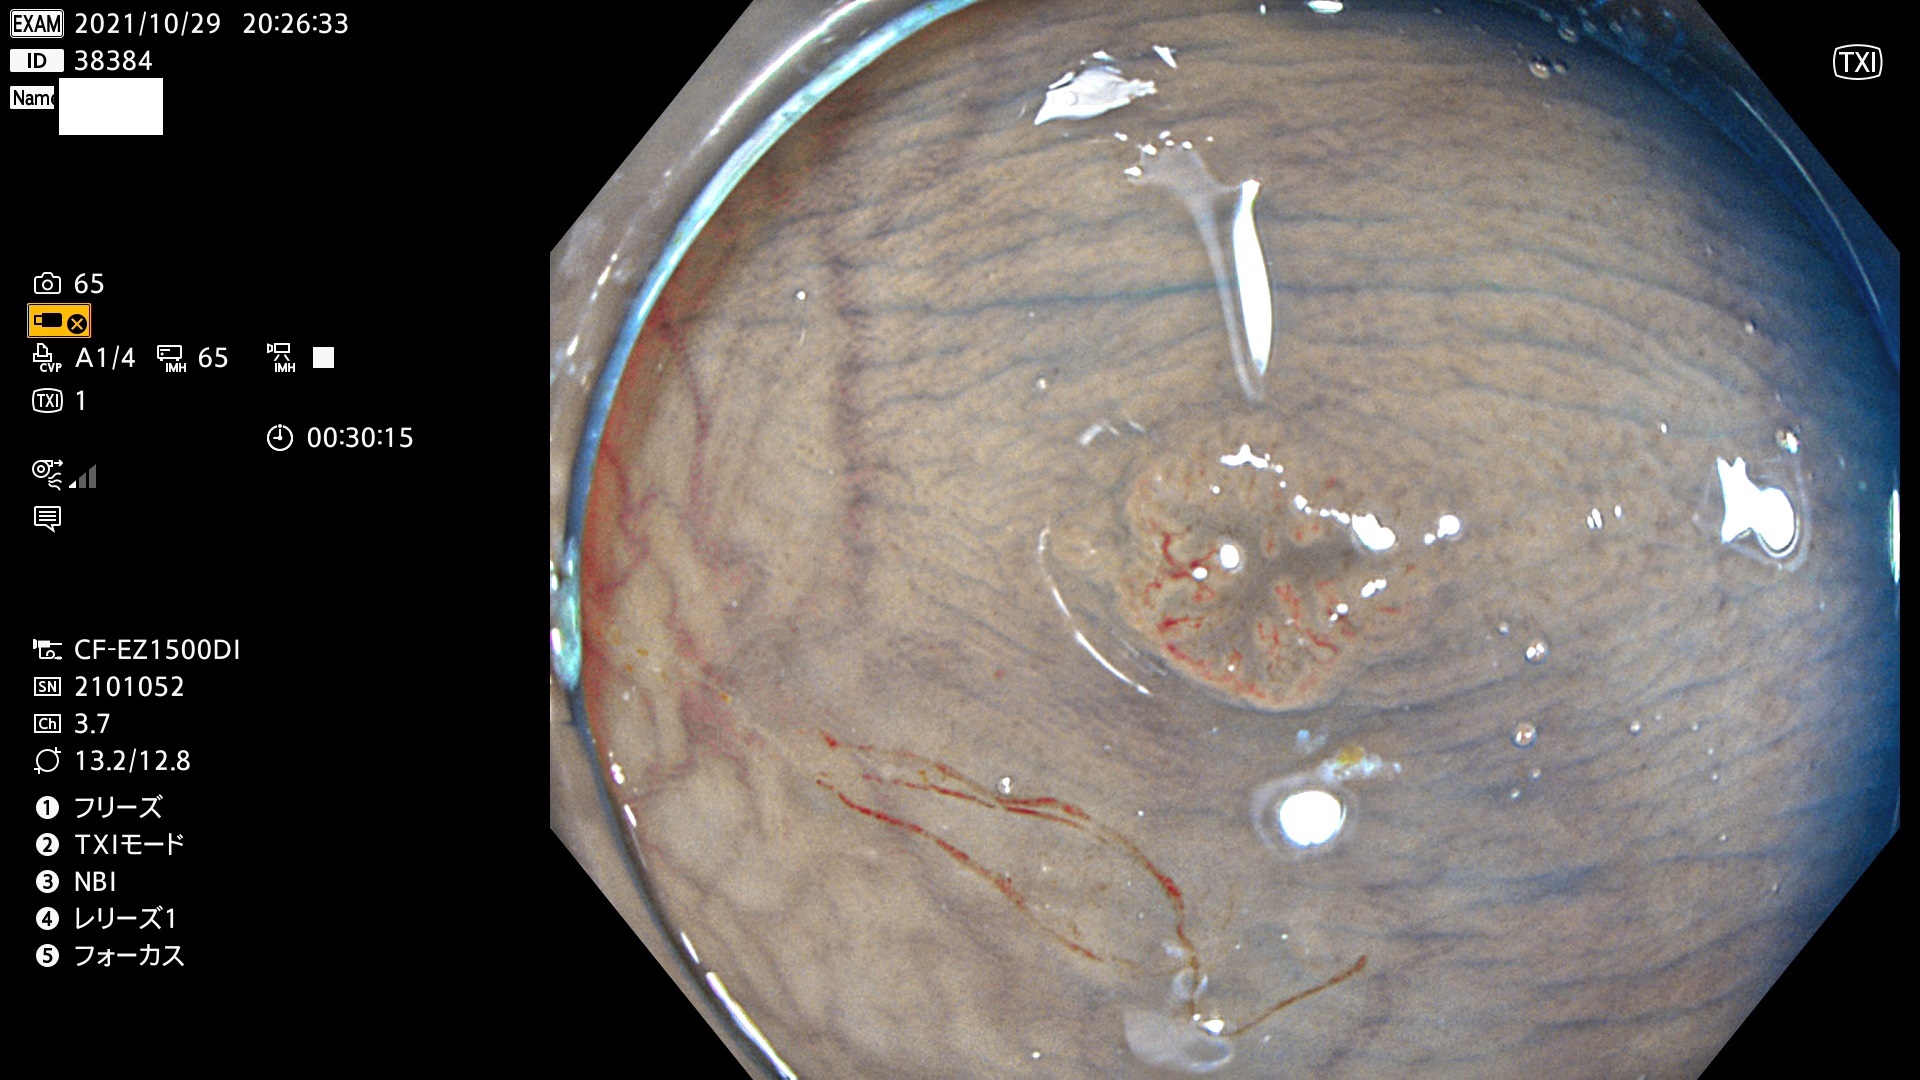

38300 38301 38302 38303 38304 38306 38307 38308 38309 38310 38311 38312 38313 38314 38315 38316 38317 38319 38321 38322 38323 38324 38325 38327 38331 38332 38333 38334 38337 38338 38339 38340 38341 38343 38346 38348 38349 38350 38351 38352 38353 38354 38355 38358 38359 38360 38361 38362 38363 38365 38366(SSAP) 38368 38369 38370 38371(SSAP) 38372 38374 38375 38376 38377 38378 38380 38381 38382 38383 38384 38385 38386 38388 38389 38391(SSAP) 38395 38397 38399

発見困難で危険性の高い平坦型病変(上記100名より抽出)